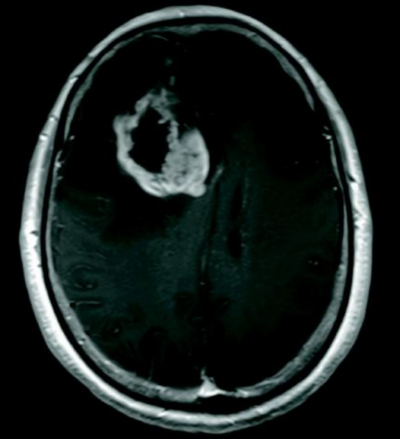

意識レベルは JCSⅠ-2。脈拍 68/分、整。血圧 142/88 mmHg。神経診察で左不全片麻痺を認める。頭部造影 MRIを別に示す。入院し、開頭腫瘍摘出術を施行した。病変部の H-E 染色標本を別に示す。

診断はどれか。

a. 膠芽腫

b. 髄膜腫

c. 脳膿瘍

d. 悪性リンパ腫

e. 多発性硬化症